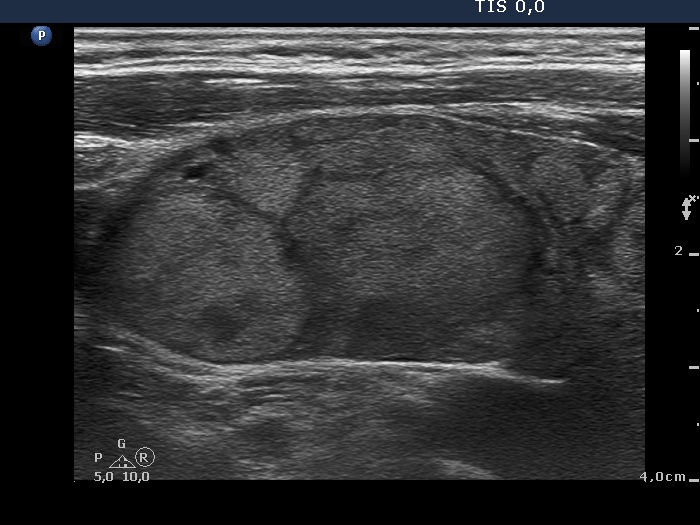

Case cons100_044 (ultrasonographic picture 6)

Left lobe, longitudinal view.